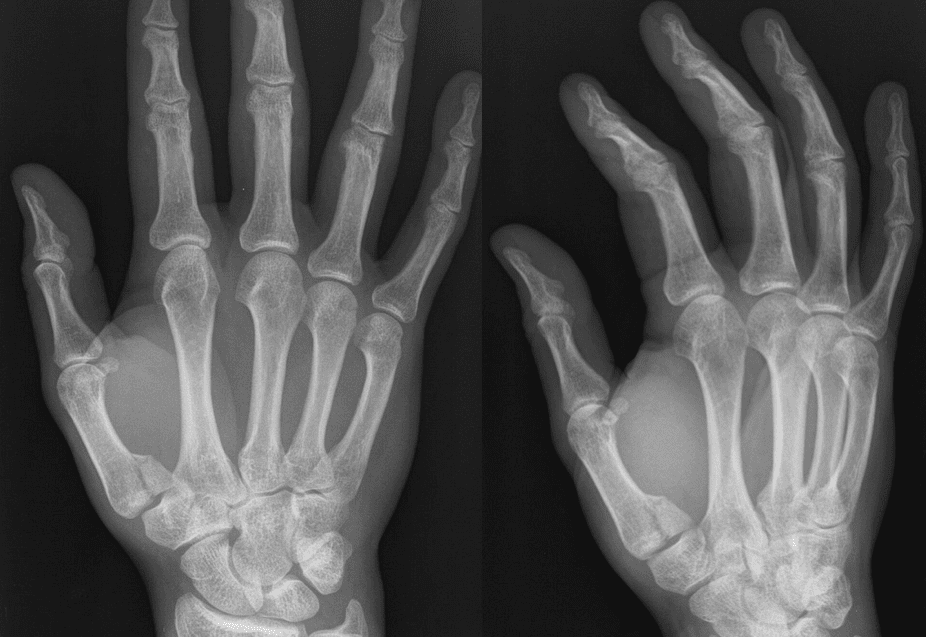

Clinical Picture

This 40-year-old male presented to the emergency department after punching another man. He felt he didn't quite time the punch correctly and his thumb connected first. The radial aspect of his hand is swollen and painful.

Xray

Quiz

Test yourself, every Sunday. How well do you know how to diagnose and treat this injury?